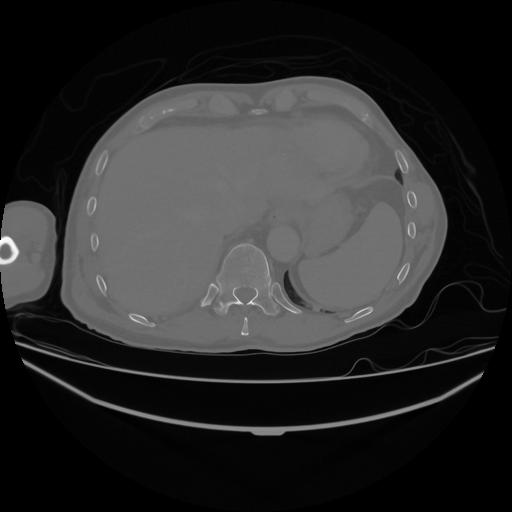

5 CUERPO,CE,Vol,1.0,CUERPO,,